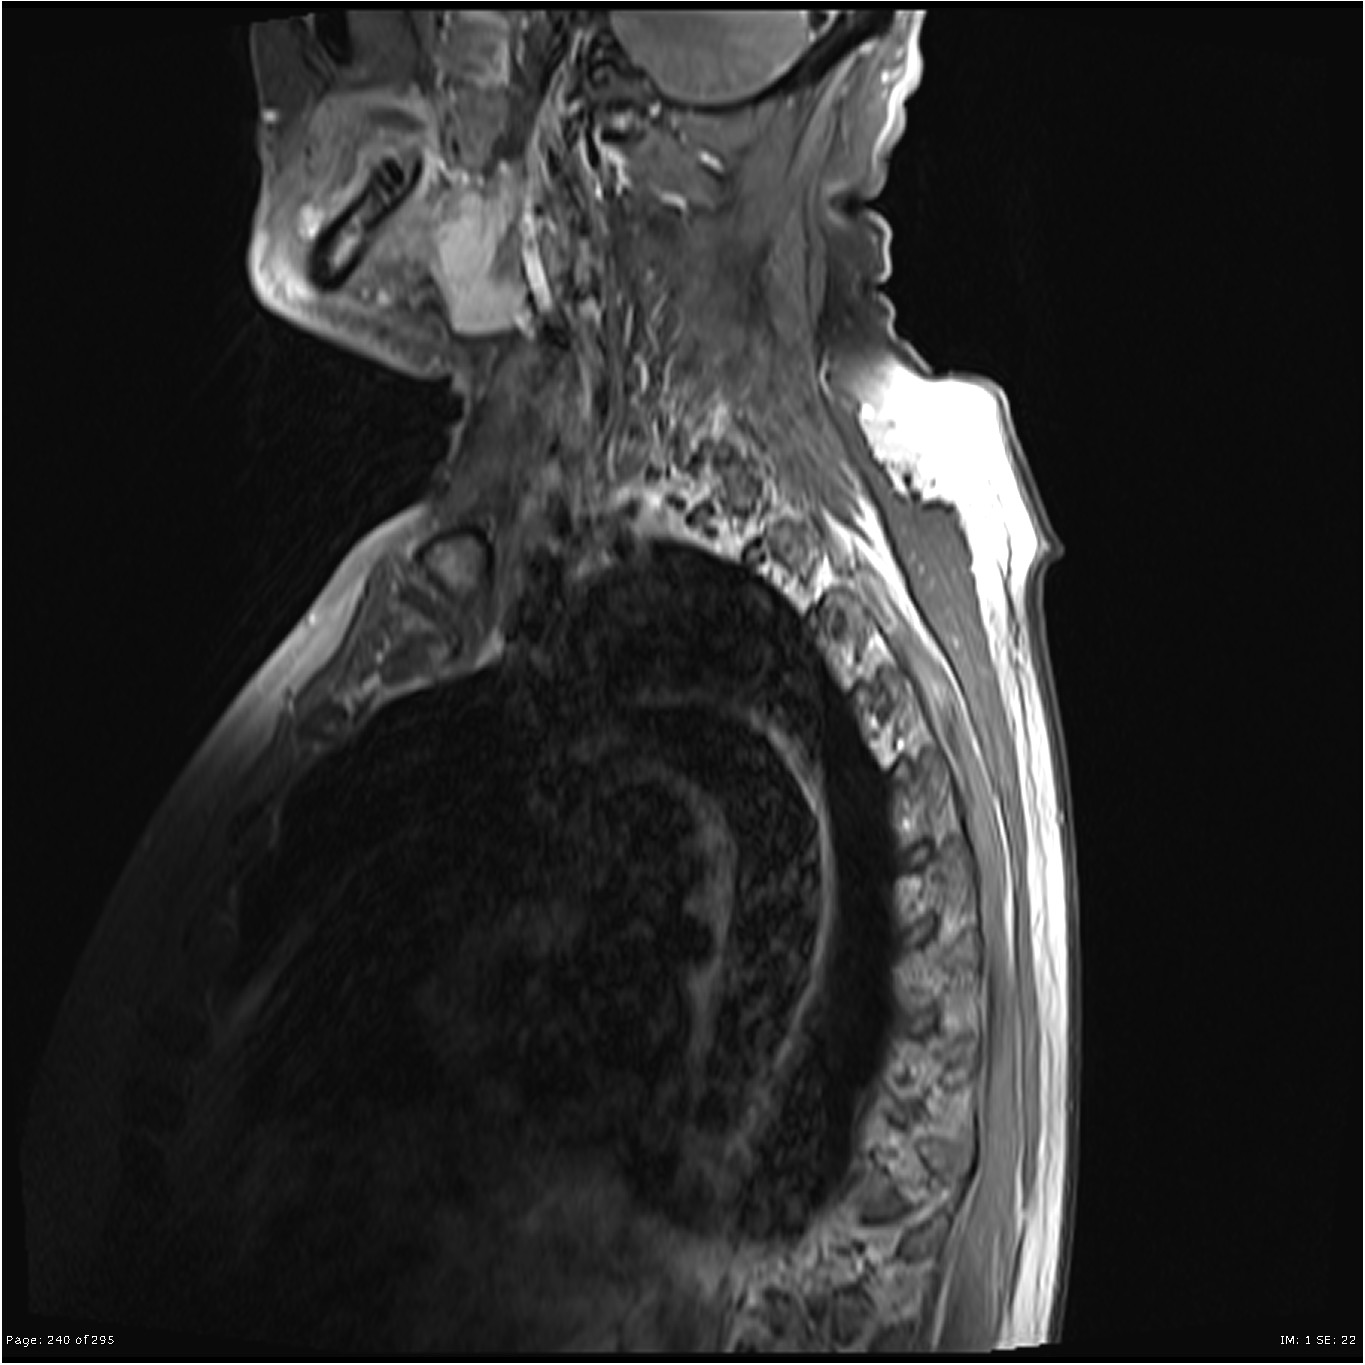

Q:脊索瘤是良性还是恶性? A:脊索瘤是一种少见的癌性肿瘤的,可以在任何地方发生沿脊柱,从头骨到尾骨的基较。脊索瘤缓慢生长,逐渐延伸到周围的骨骼和软组织中。它们经常在...

Q:脊索瘤不开颅可以治吗? A:脊索瘤是少见的脊索残余源性恶性肿瘤,通常更常见于男性,发病率在50至60岁之间。它们主要是粘液样,伴有肿瘤内钙化及区域性出血。常见部位位于骶...